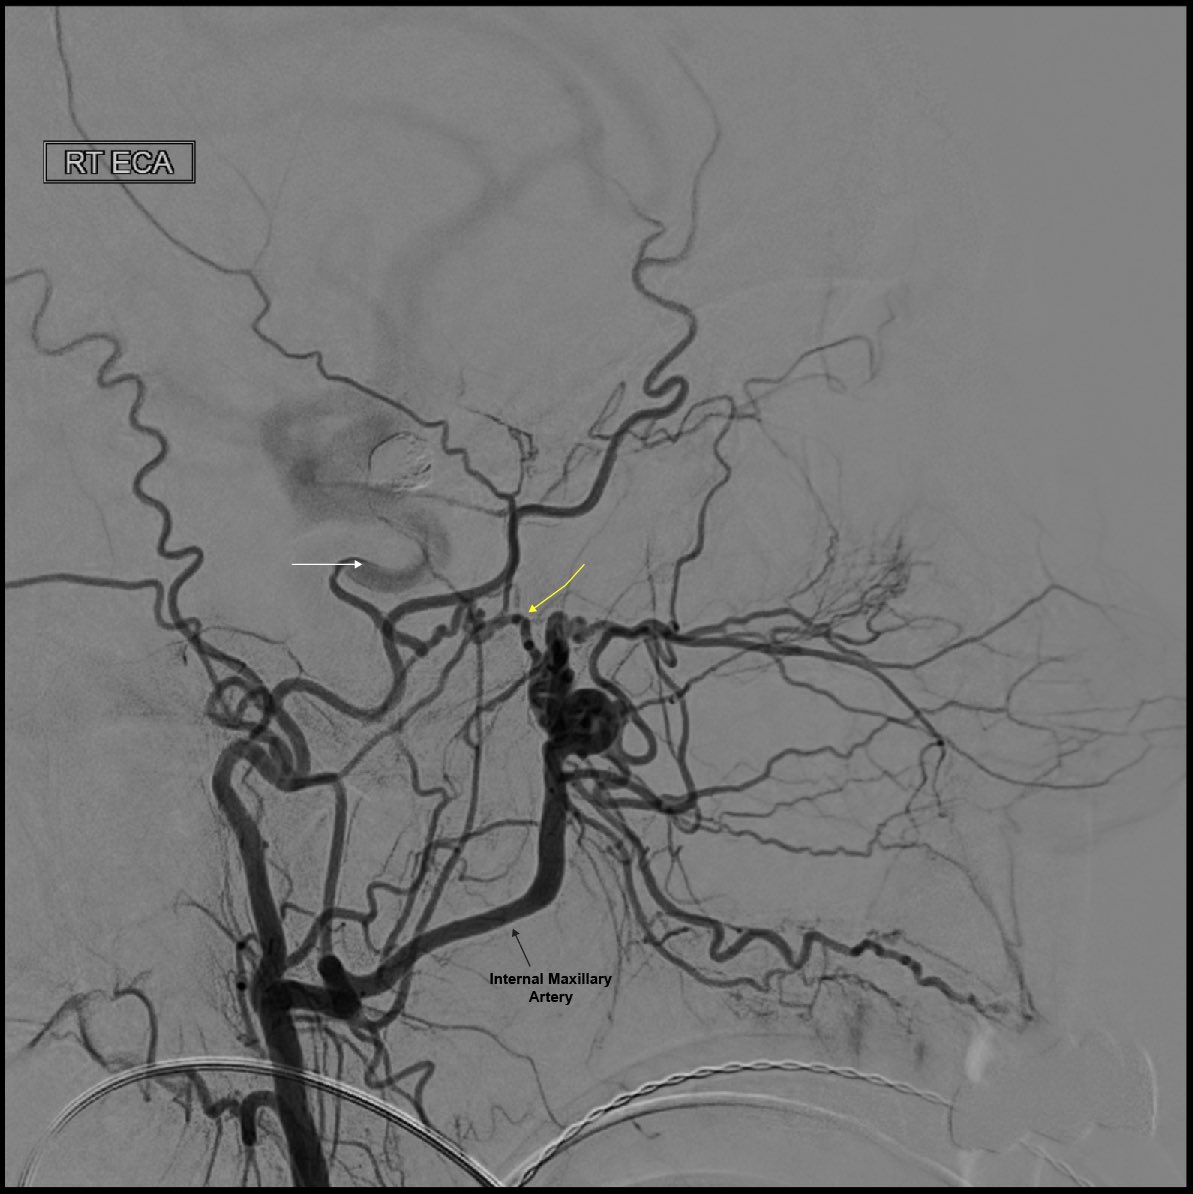

@YNIScommittee Likely an enlarged Artery of the Foramen Rotundum connecting to the ICA via the inferolateral trunk